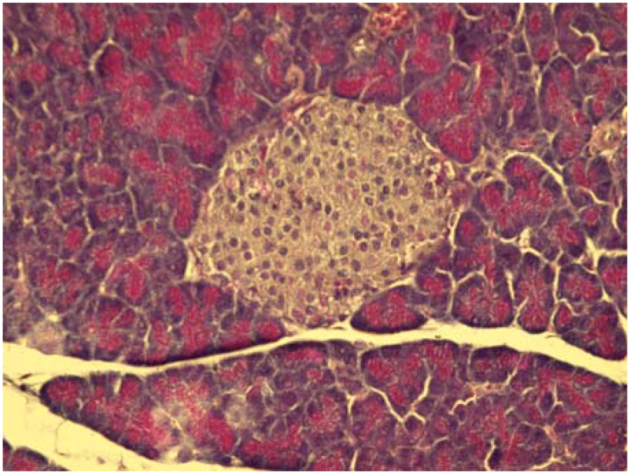

Figure 2.

Microphotograph of the pancreas of control mice (HE 400×). Pancreatic islets with distinctly-outlined cell borders (physiological findings).

On the other hand, some cytoprotective effect of diplacone (1) was proved by histopathological analysis of pancreatic tissue (Figure 2, Figure 3, Figure 4, Figure 5). This observation supports fact that flavonoids may act as a cytoprotective substances [29]. Results of cytoprotective activity assay could be correlated with a higher activity of diplacone (1) compared with the other tested compounds.